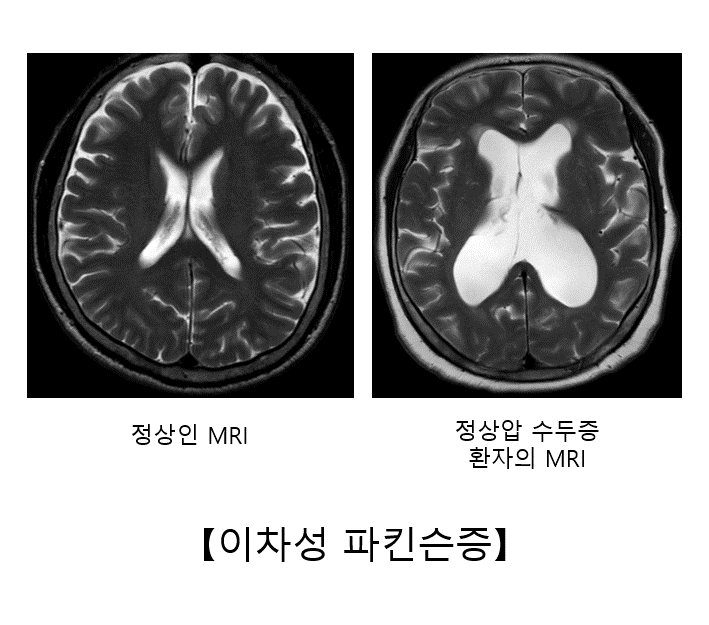

② 정상압 수두증

정상압 수두증은 뇌척수액이 원활하게 순환되지 않아 뇌실이 확장되면서 주변 뇌를 압박하여 정상적인 기능에 장애를 초래하는 질환을 말합니다. 정상압 수두증의 가장 주된 증상은 보행 장애입니다. 환자는 발을 넓게 벌리고 종종걸음을 걷습니다. 파킨슨병처럼 운동 완만이나 체위 불안정도 흔하게 나타납니다. 배뇨 장애와 인지 기능의 저하가 동반되는 경우가 많습니다.정상압 수두증은 뇌 전산화 단층촬영(CT)이나 뇌 자기공명영상(MRI)에서 뇌실이 커져 있는 소견이 확인됩니다. 척수 천자를 통해 뇌척수액을 배액했을 때 일시적으로 파킨슨 증상이 호전되면 진단할 수 있습니다. 이러한 경우 뇌실복강션트라는 수술을 하면 지속적으로 뇌척수액을 배액하여 증상을 호전시킬 수 있습니다.